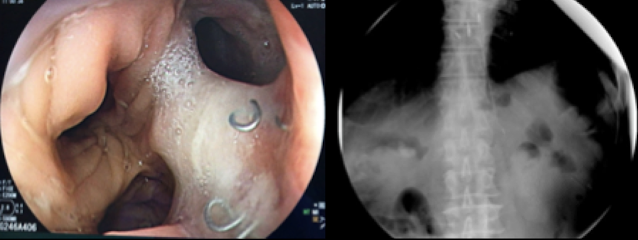

Se decidió iniciar cobertura antibiótica con piperacilina/tazobactam, NPT y solicitar exámenes de imagen. La tomografía reveló falta de continuidad y afrontamiento de anastomosis esófago-yeyunal con separación de suturas metálicas, asociado a pequeñas colecciones adyacentes con contenido aéreo y, el tránsito intestinal mostró fuga de contraste hacia hipocondrio derecho con trayecto de salida hacia dren y bolsa colectora.

En el caso presentado se pueden reconocer los factores descritos como predictores del buen resultado obtenido, ya que se trataba de un paciente operado de gastrectomía total, clínicamente estable (y con adecuados parámetros nutricionales), a quien se colocó el SEMS de forma temprana (PO15) para sellar un defecto menor de 20 mm, siendo ésta medida un punto de corte sugerido en el estudio de Rodrigues-Pinto et al.(11)